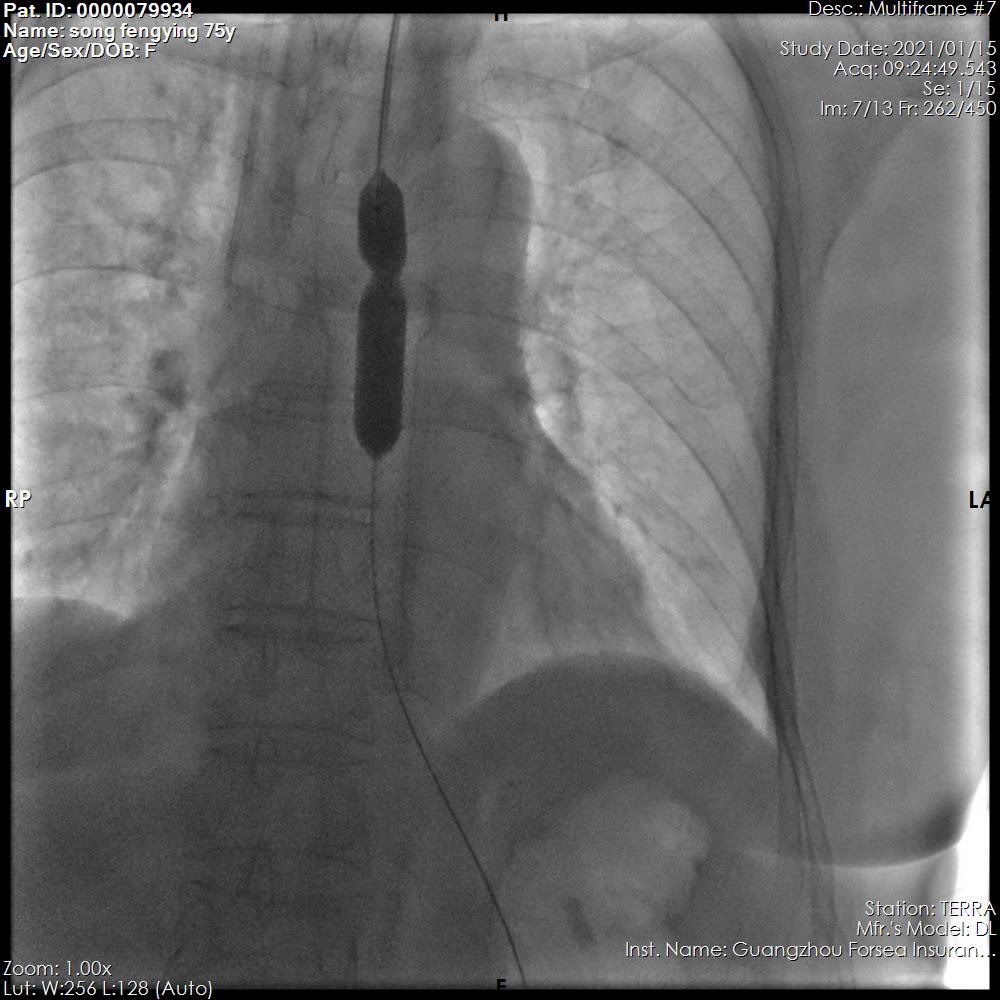

狭窄部位经过球囊扩张

支架经推送器放至狭窄部位